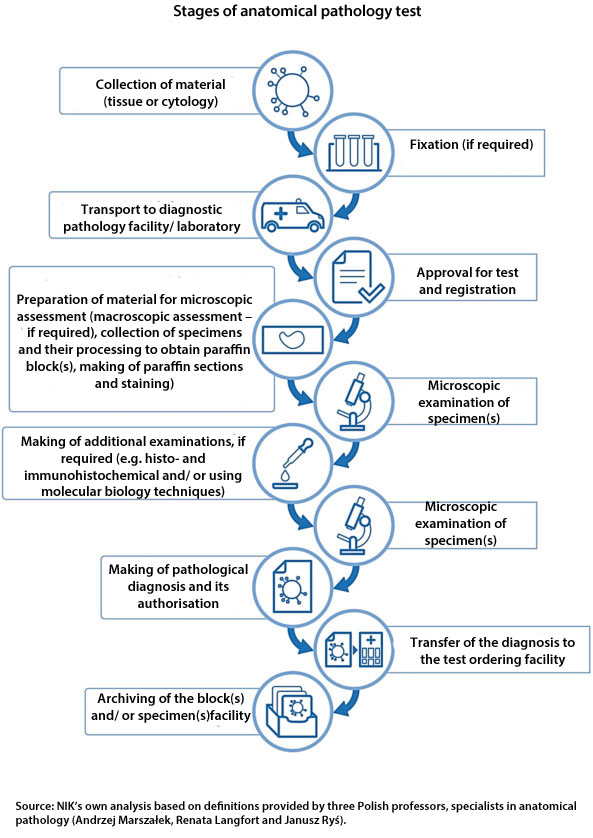

NIK about diagnostic pathology - Supreme Audit Office

Pathologic diagnosis is a step-by-step process starting with good